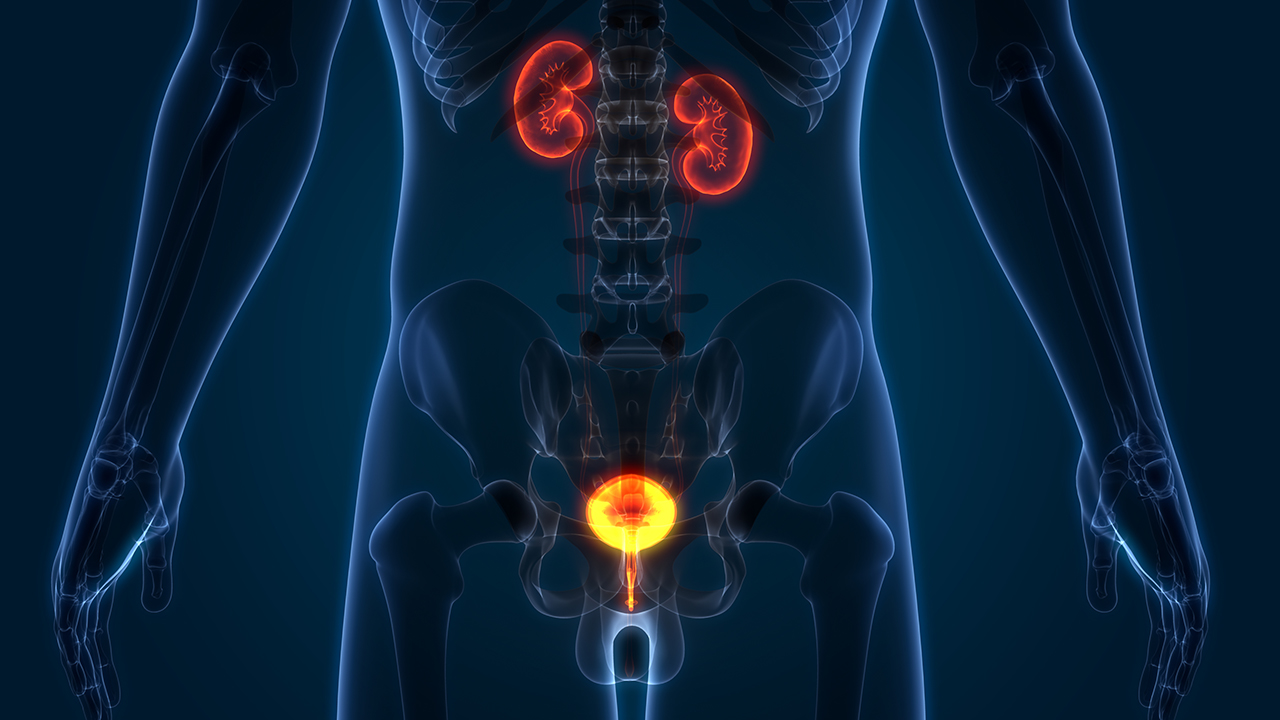

前列腺psa高怎么治疗

前列腺PSA升高需先明确原因如前列腺癌、增生、炎等并通过直肠指检等检查明确,针对不同病因治疗,增生者可观察、药物或手术,前列腺炎者用抗生素等对症,前列腺癌者手术、放疗或内分泌治疗,老年及合并基础病者需关注特殊情况治疗要个体化并考虑特殊情况制定合理计划。